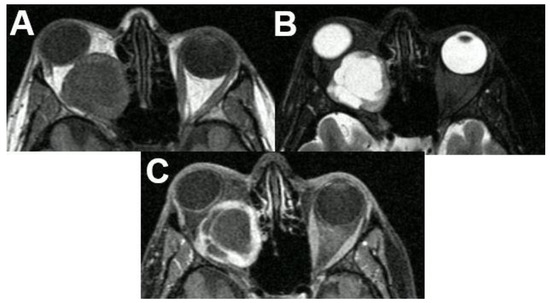

3.2.2. Cavernous Hemangioma

3.3. Extraconal Tumors